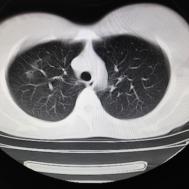

支原体肺炎1例CT影像表现

性别:女,年龄:26岁,低热,轻微胸痛,支原体阳性

两肺内及胸膜下多发斑片状高密度影,部分病灶密度较淡,部分实变,边缘可见渗出改变。

支原体肺炎是由支原体引起的以间质改变为主的肺炎。实验室检查支原体抗体呈阳性。支原体侵入肺内可引起支气管、细支气管黏膜及其周围间质充血、水肿,多核细胞浸润,侵入肺泡可产生肺泡浆液性渗出性炎症。CT早期主要改变为肺间质炎症,病变区肺纹理增粗而模糊,病变范围广泛,常累及多个肺叶,单侧或双侧的磨玻璃影及实变影,以双肺下叶多见,多呈小叶性分布。同时,患者的临床症状与CT改变不匹配,即临床症状明显好转或消失但肺部阴影吸收不明显。鉴别诊断:支气管肺炎好发于两中下肺的内、中带,病灶沿支气管分布,呈多发散在小的斑片状影,常合并阻塞性小叶性肺气肿或小叶性肺不张,结合临床多见于婴幼儿或年老体弱者。渗出浸润为主的继发性肺结核病灶表现为结节状或呈不规则斑片状影,边缘较模糊,密度不均匀,病灶内可见小空洞。增殖性病灶密度较高,边缘清楚,病灶内或周围可见不规则钙化灶。浸润性病变常与纤维化并存,可伴有邻近支气管扩张。结核分枝杆菌检查阳性。